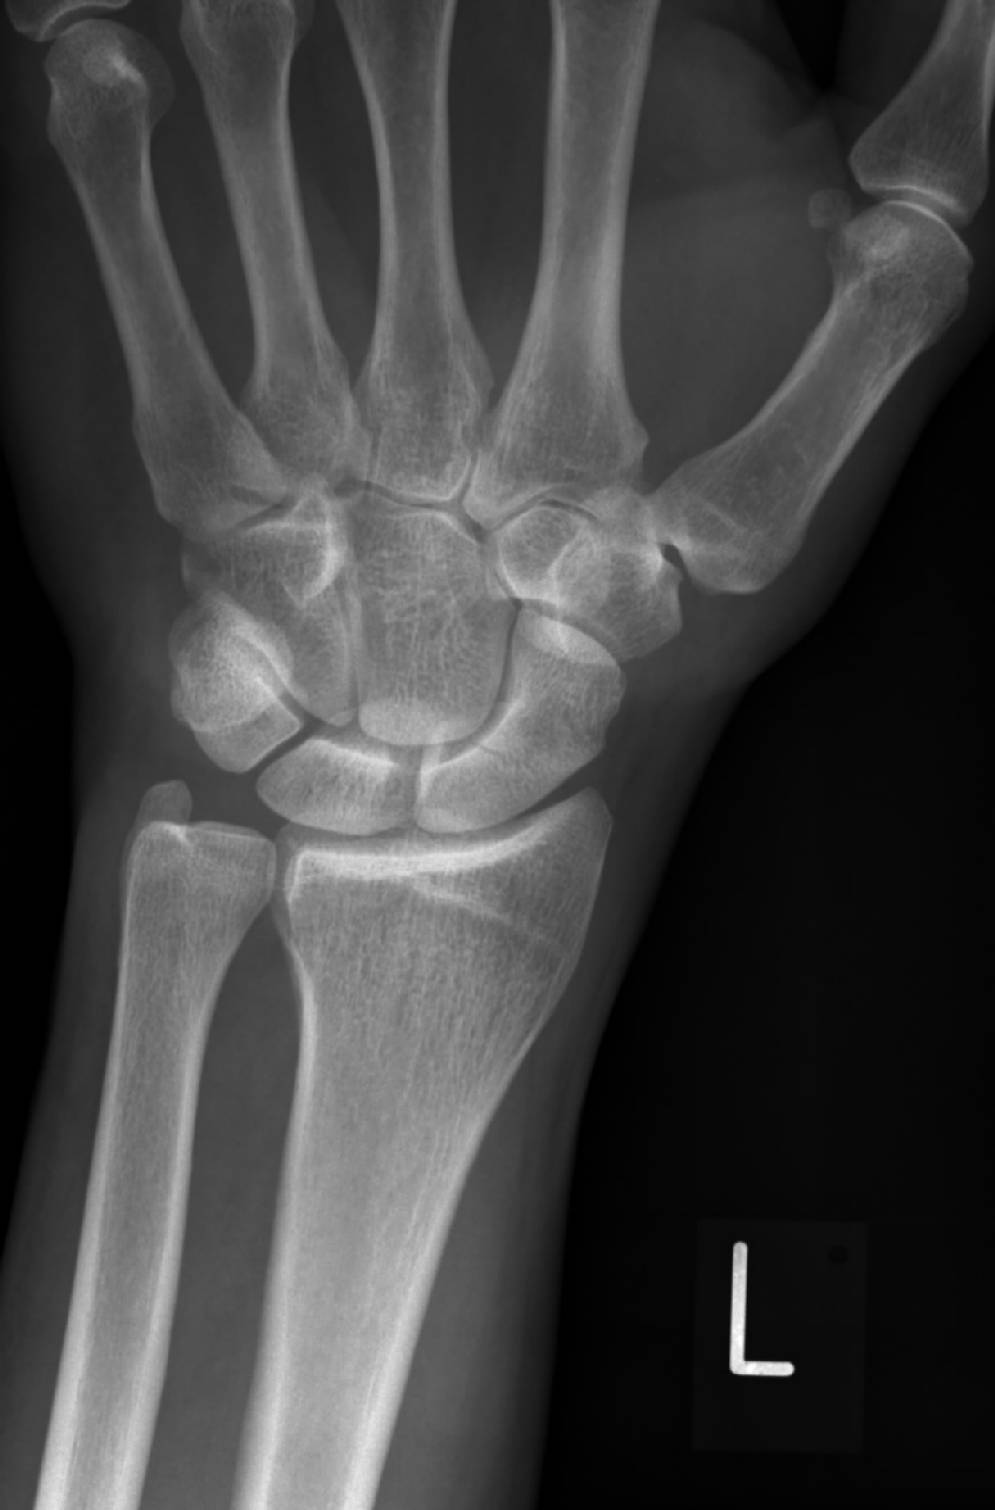

Handwurzelknochen Fraktur

Fraktur Handgelenk Symptome